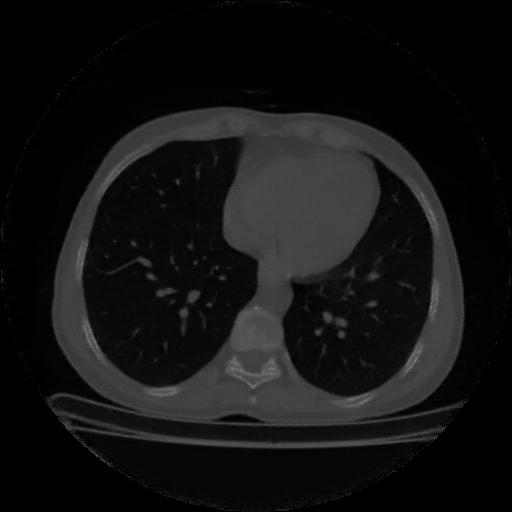

Image Grid

4×3 grid: Rows show different image types (Original NATIVE, Reconstructed NATIVE, Original VENOUS, Generated VENOUS), Columns show windowing techniques (No Window, Lung Window, Mediastinum Window)

Reconstructed NATIVE CT scan (cycle consistency)

No window - Raw intensity values

Reconstructed NATIVE CT scan (cycle consistency)

Lung window (WL -600, WW 1500 → Low −1350, High +150)

Windowing Parameters

- No Window: Raw intensity values without windowing

- Lung Window: WL -600, WW 1500 → Low −1350, High +150 (optimal for pulmonary structures)

- Mediastinum Window: WL 40, WW 400 → Low −160, High +240 (optimal for soft tissues)